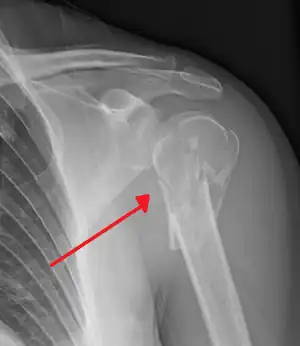

Proximal humerus fracture

| Multi-fragmented fracture of the proximal humerus with involvement of the greater tuberosity | |